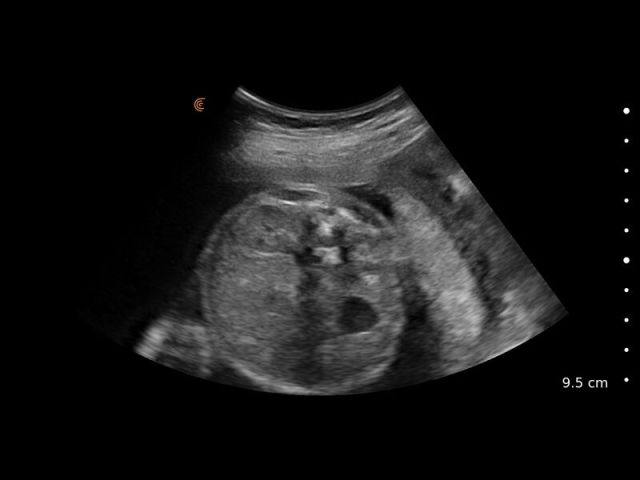

Medical professionals love the high portability, easy of use, and high-definition imaging of the Clarius C3 HD3 multipurpose scanner for full body imaging up to 40 cm. It’s the leading choice for medical professionals looking for premium imaging in an affordable scanner. Artificial intelligence, specialized presets and customizable workflows automatically optimize imaging for a seamless experience.

Applications: Abdominal, Cardiac, Lung, OB/GYN, Superficial

Clinical Images